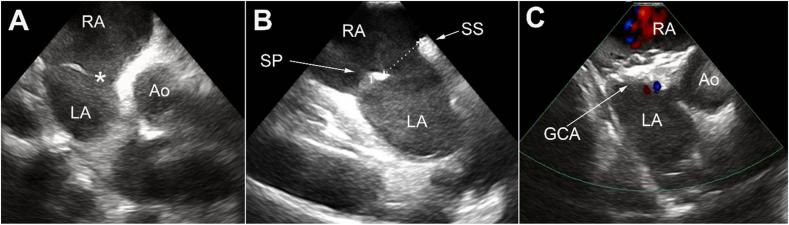

Percutaneous closure of ASD is nowadays preferred and more widely performed over surgical closure. The GORE® CARDIOFORM ASD occluder (GCA) is the latest generation of occluder with promising results as it performed well with high successful implant rates (96%) and showed high efficacy in challenging clinical and anatomical situations. We present the case of a 65 female with a 2.5 cm ASD, left atrial hypertension, deficient retroaortic rim, mobile septum primum and hypertrophied septum secundum. She underwent uncomplicated closure with a 44-mm GCA. However, the patient presented to the emergency room five weeks post procedure and was found to be in atrial fibrillation with rapid ventricular response at a rate of 158 bpm. Further workup showed a dislodged GCA device despite appropriate device placement and size selection based on the published instructions for use. We elected to not remove the 44-mm GCA given that it had become adherent to the septum primum but instead used the stiffer Amplatzer septal occluder to stabilize the GCA and occlude the residual defect. Finally, we highly recommend taking device destabilizing factors into consideration when selecting device size.

如今,经皮封堵房间隔缺损(ASD)比外科手术封堵更受青睐且应用更为广泛。戈尔公司的CARDIOFORM ASD封堵器(GCA)是新一代封堵器,取得了令人瞩目的成果,其植入成功率高(96%),在具有挑战性的临床和解剖情况下也显示出高效性。我们报告了一例65岁女性患者,患有2.5厘米的房间隔缺损、左心房高压、主动脉后缘不足、原发隔活动及继发隔肥厚。她使用44毫米的GCA进行了顺利封堵。然而,患者在术后五周因快速心室反应性房颤(心率158次/分钟)就诊于急诊室。进一步检查发现,尽管根据已发布的使用说明进行了合适的装置放置和尺寸选择,但GCA装置仍发生了移位。鉴于44毫米的GCA已与原发隔粘连,我们选择不取出它,而是使用更硬的Amplatzer房间隔封堵器来稳定GCA并封堵残余缺损。最后,我们强烈建议在选择装置尺寸时考虑装置不稳定因素。